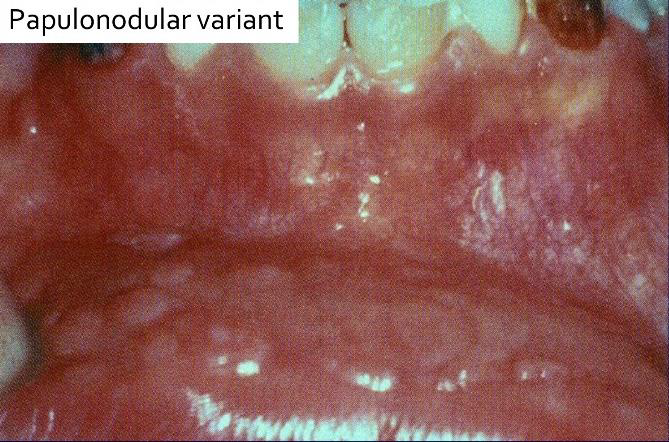

| Multifocal epithelial hyperplasia (Heck’s disease, 13, 32) |

低社經、HIV | 唇、頰、舌 | 小、軟、多、無痛 | |||

Papillomatous variant

|

Papulonodular

|